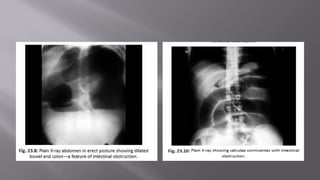

 Jejunum shows concertina effect due to valvulae conniventes

(Herring bone pattern)—by the valves of Kerckring.

 Ileum is smooth and characterless (by Wangensteen).

 Large bowel shows haustration.

 Distended caecum is shown as round gas shadow in the right

iliac fossa. Dilated caecum signifies large bowel obstruction.